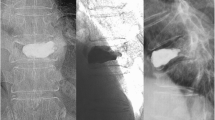

Cement distribution patterns also correlated well with bone marrow integrity, which may influence the prognosis of cemented vertebrae. In a fat-suppressed contrast-enhanced MRI study [15], a solid distribution pattern of injected cement was observed in all unenhanced areas, while outside the unenhanced area a solid pattern was not observed. Technically, the unenhanced areas, which are usually located anterior-superiorly, tend to be filled easily during the procedure. The minimal resistance from the cleft was prone to leaving the posterior enhanced area unfilled. The higher the unenhanced volume ratio of injured vertebrae, the more intravertebral space would be replaced by rigid cement. This suggests that crushing of the unfilled, small, enhanced part of the injured vertebrae by the cemented portion is inevitable (Fig. 3).

Images of a 62-year-old man. T2-weighted images (a) and T1-weighted-enhanced fat-suppression images (b) show a large, poorly enhanced zone in the L1 vertebra (arrow). c Plain radiographic image immediately after vertebroplasty. (d) Follow-up MRI 1 month after the procedure showed a recurrent fracture with increased enhancement of the inferior-posterior vertebra. e Further collapse of the treated vertebra was found 6 months after vertebroplasty